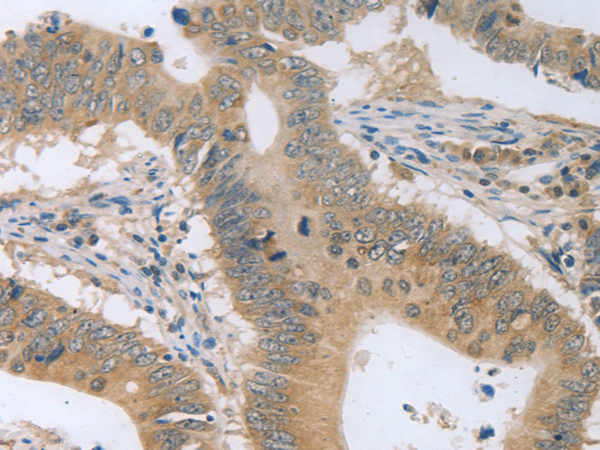

分类: 科研抗体货号: P11292别名: DTD, QR1, DHQU, DIA4, NMOR1, NMORI应用: WB,IHC反应种属: Human, Mouse, Rat